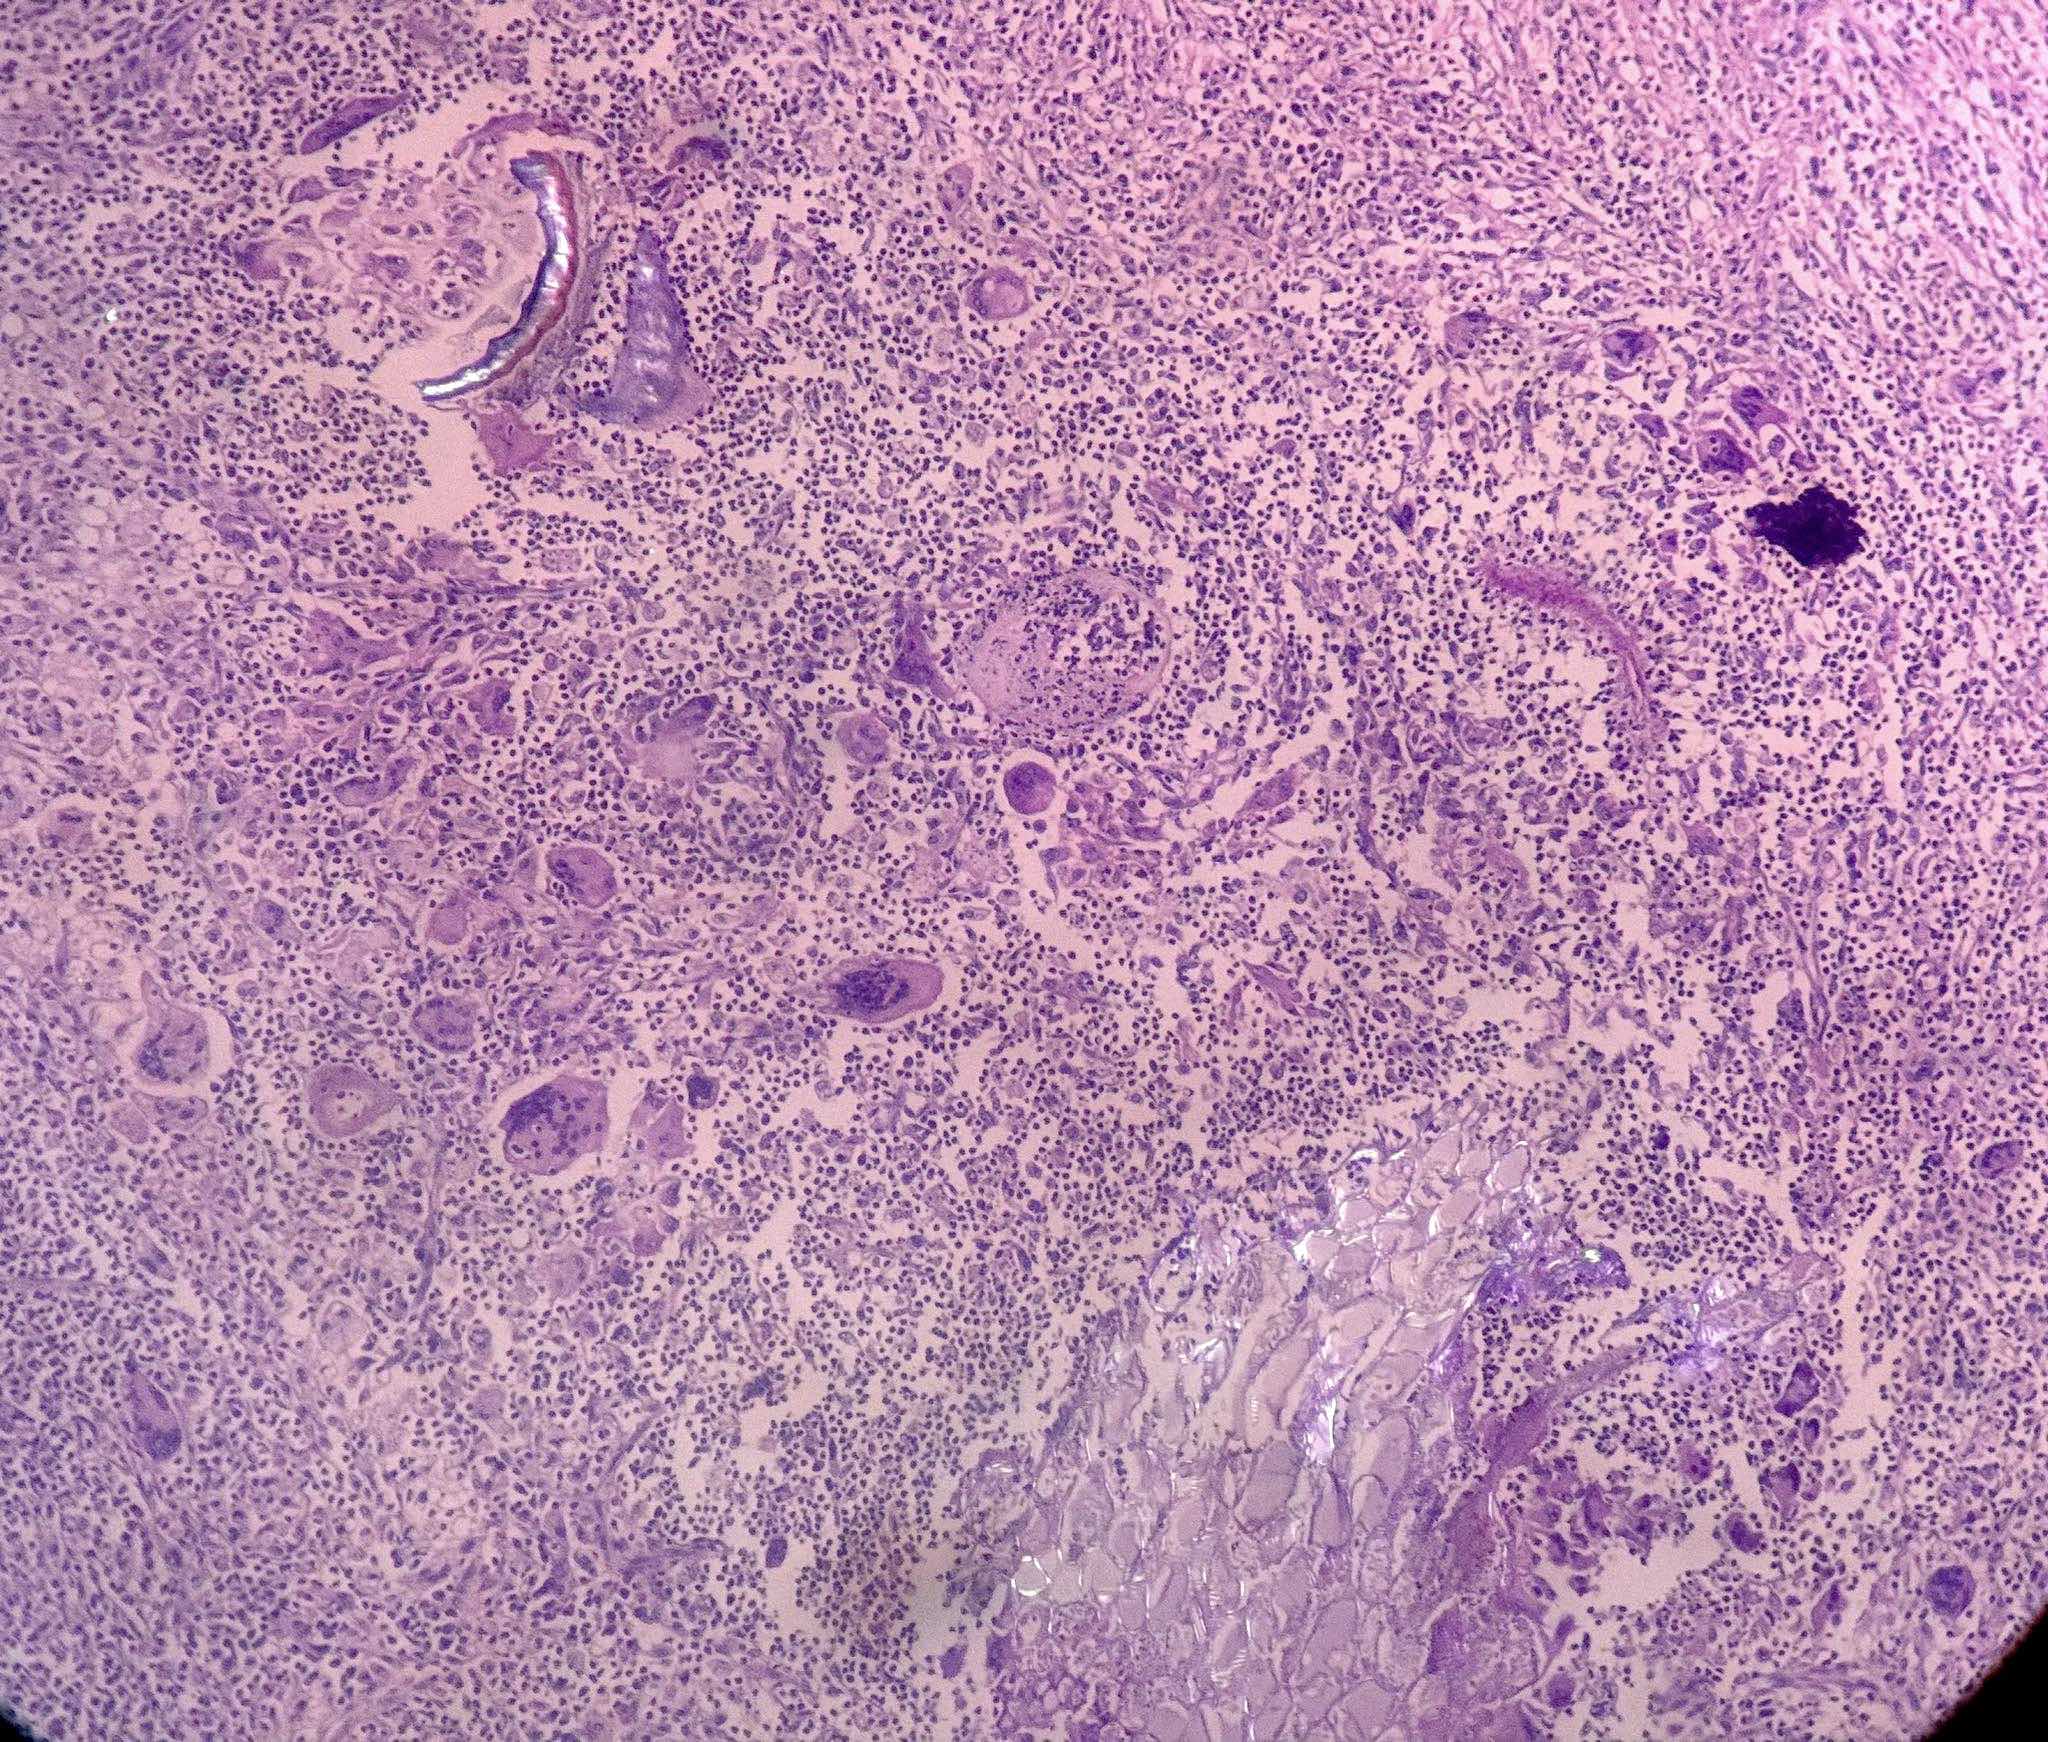

Microscopic (histologic) description

- Lobar pneumonia (Semin Diagn Pathol 2017;34:498):

- Uniform inflammatory infiltrate, the changes are at the same stage throughout the entire lobe

- Early stage: vascular engorgement, intra-alveolar fluid with few neutrophils and often bacterial colonies

- Massive confluent exudate with intra-alveolar neutrophils, red cells and fibrin, correlates with red hepatization on gross exam

- Progressive disintegration of red cells and the persistence of a fibrinosuppurative exudate, correlates with gray hepatization on gross exam

- Resolution phase: exudates converted to fibromyxoid masses rich in macrophages and fibroblasts

- Usually resolves with minimal fibrosis

- Pleuritis can be seen

- Bronchopneumonia:

- Most common pattern of pulmonary infection

- Different stages in the different areas

- Patchy intra-alveolar fibrinopurulent exudate with neutrophils

- Acute lung injury pattern:

- Diffuse alveolar damage (DAD): hyaline membrane formation

- Organizing pneumonia (OP): fibrohistiocytic proliferation with obliteration of small airways (fibroblast plug, Masson body), accompanied by inflamed surrounding alveolar interstitium

- Necrotizing pneumonia (Can Respir J 2014;21:239):

- Characterized by necrotizing inflammation, leading to alveolar septa disruption and cavity formation

- Common organisms: Staphylococcus aureus, Streptococcus pyogenes, S. pneumoniae (certain serotypes), Klebsiella, Acinetobacter, Pseudomonas and Burkhodoria

- Aspiration pneumonia:

- Foreign body giant cell reaction, characterized by multinucleated giant cells, granulomatous inflammation

- Often necrotizing, abscess formation is common

- Presence of food particles (e.g., lentils, vegetables, pill fragments)

Microscopic (histologic) images